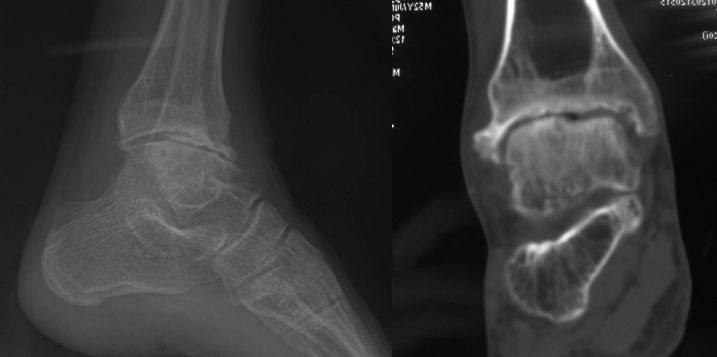

外踝骨折

王岩  男  24岁

软组织撞击

术后复查